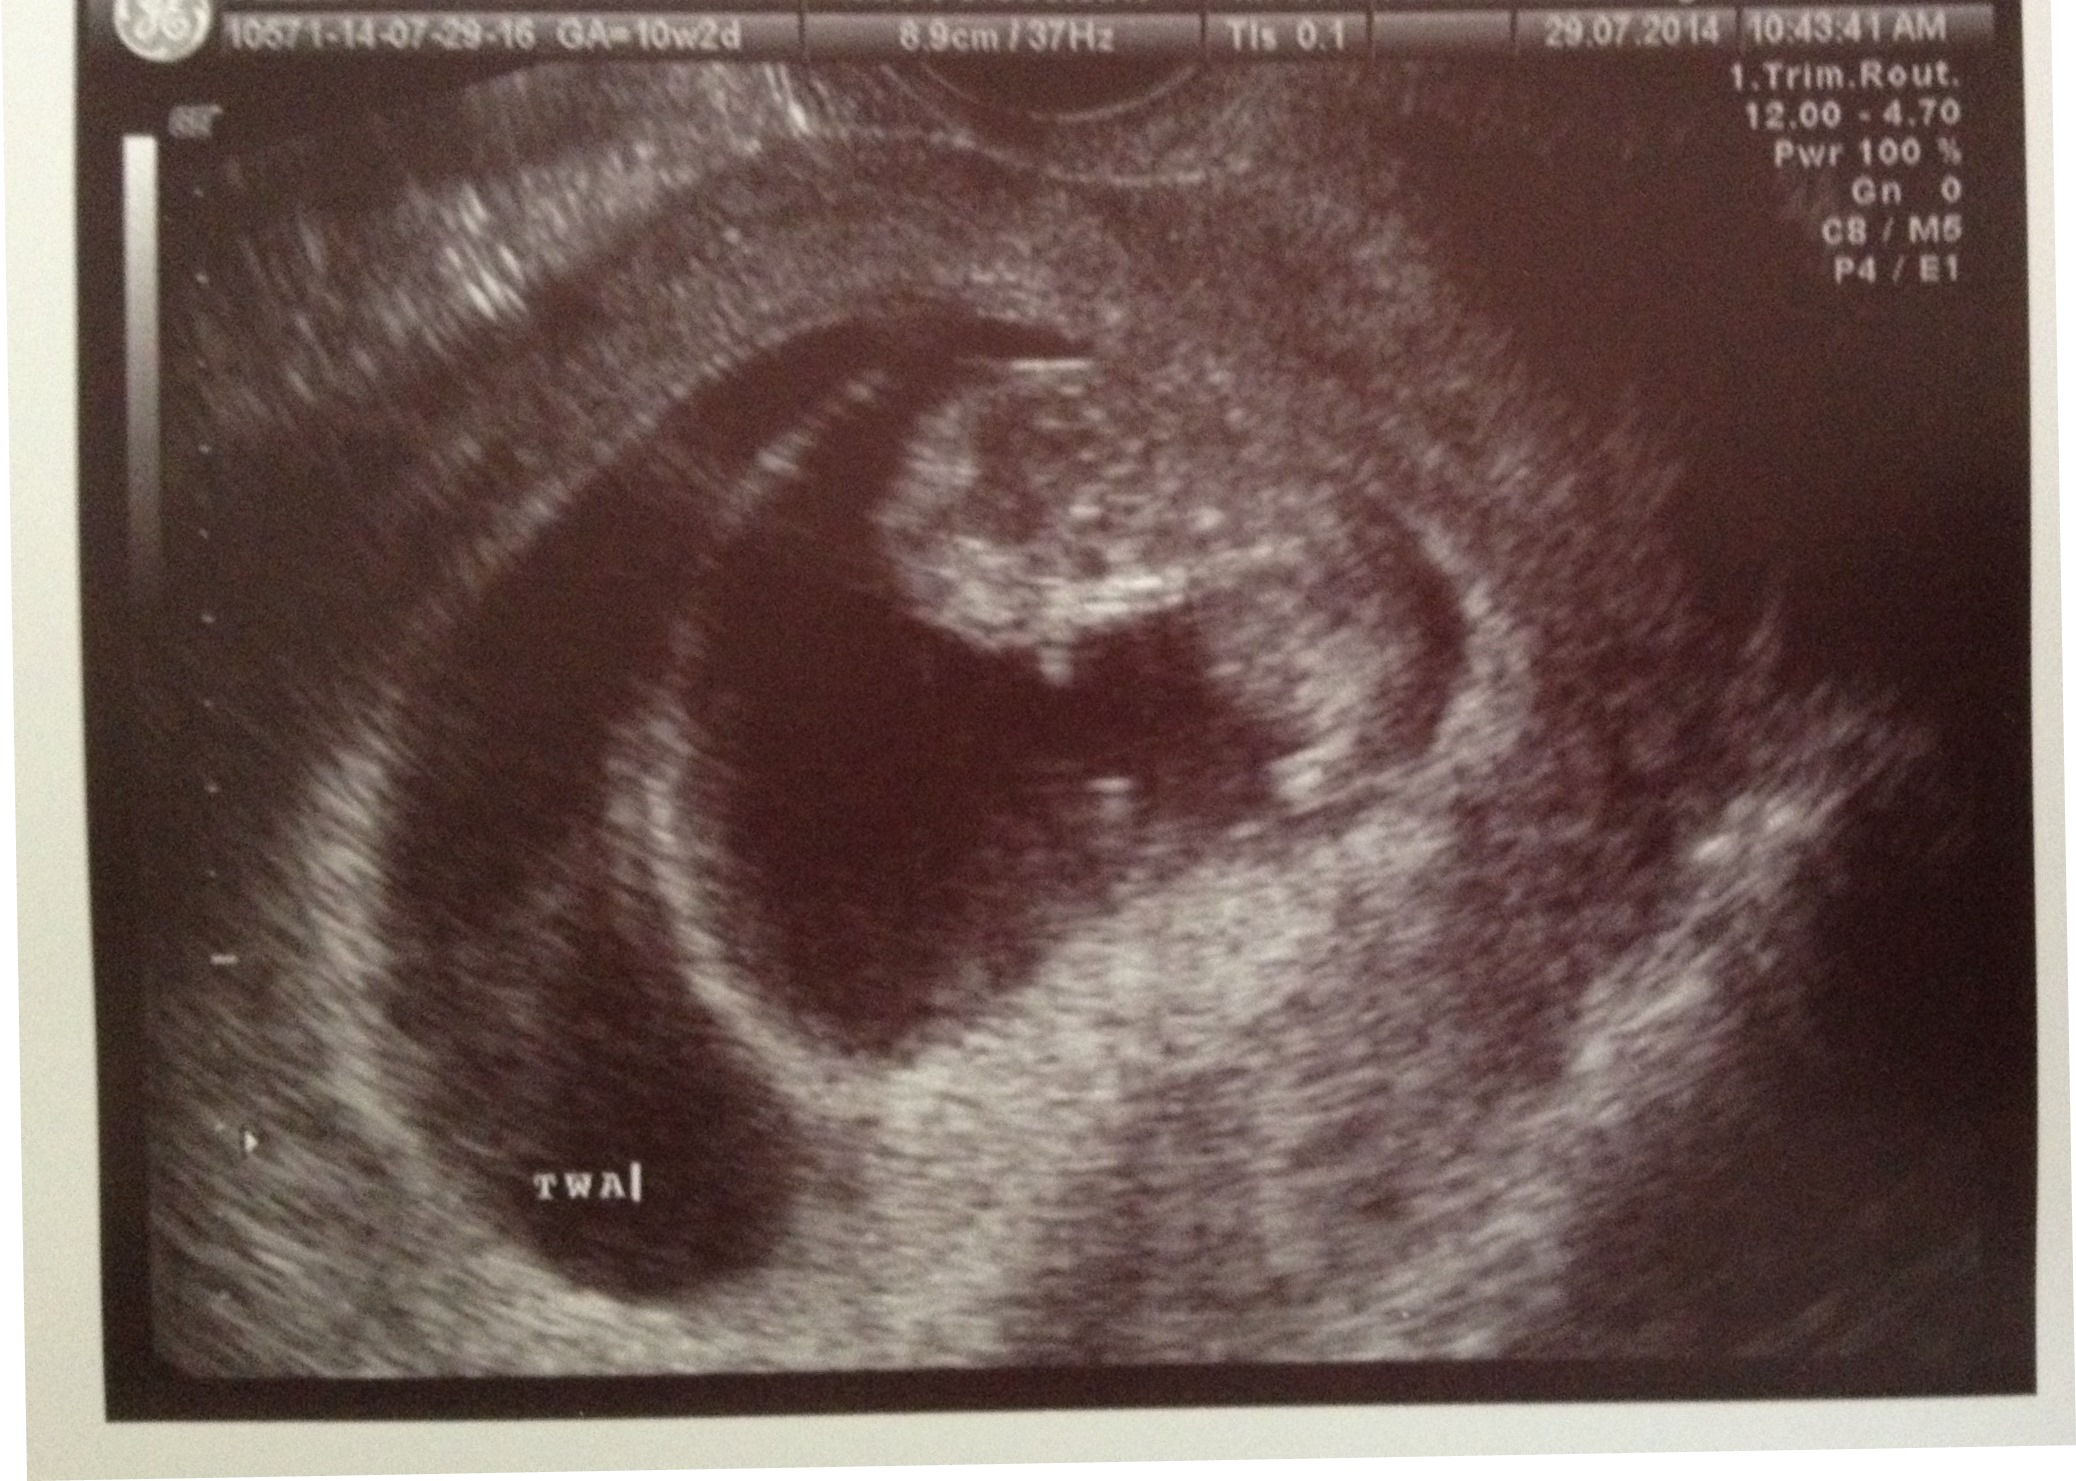

Ultrasound set for 2/17/14......TWINS! Twin A - HR 124 bpm; Twin B - HR 126 bpm

Final Ultrasound with RE 3/10/14 - Twin A - HR 176 bpm; Twin B - HR 177 bpm.